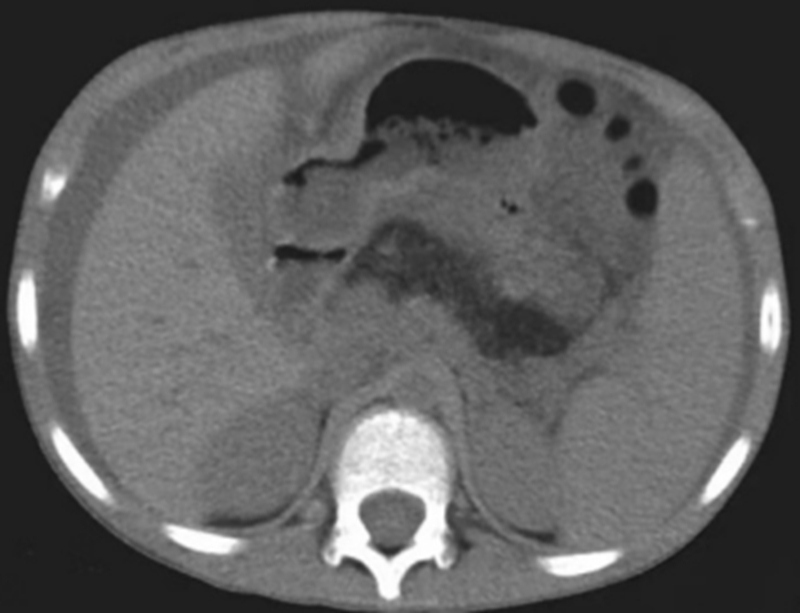

CT 所示胰腺區(qū)脂肪密度影

該病十分罕見,患兒常以脂肪瀉、肝酶異常為首發(fā)癥狀,隨后會(huì)出現(xiàn)反復(fù)感染、生長(zhǎng)緩慢、骨骼異常、血細(xì)胞減少等表現(xiàn),需要通過(guò)大便脂肪含量、血清胰酶、胰腺影像學(xué)、骨髓細(xì)胞學(xué)分析及基因檢測(cè)才能最終確診。